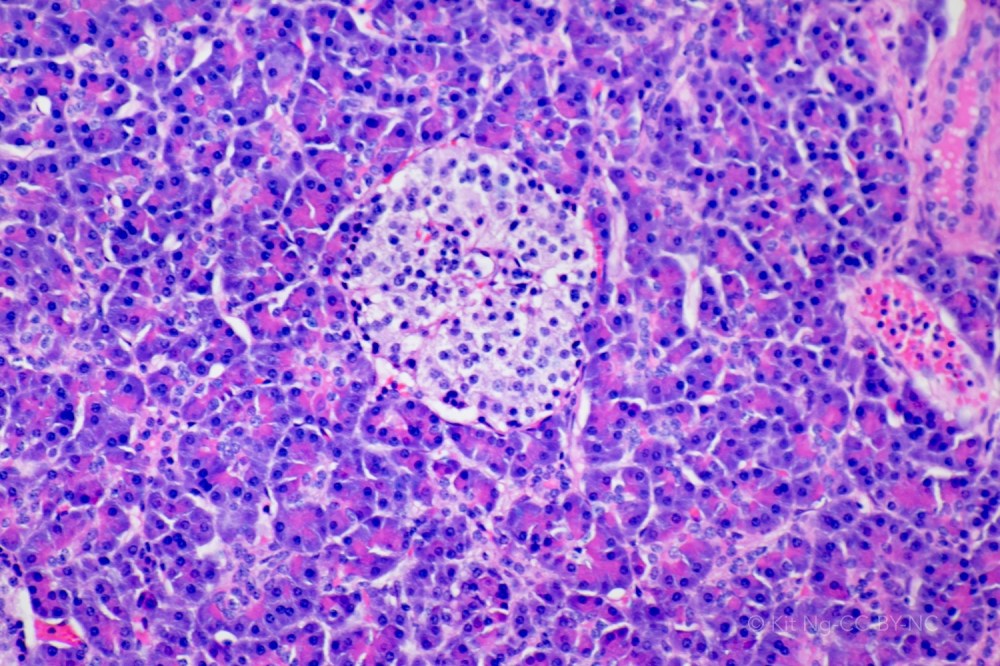

The pancreas is a retroperitoneal organ located behind the stomach. The organ is organized into lobes. The relationship between the pancreas and other organs can be viewed in the model here. Microscopically the organ has two parts – the endocrine part consists of the Islets of Langerhans, and the exocrine part consists of the acini.

The Islets of Langerhans are composed of three types of cells: Alpha, Beta, and Delta. These cells produce glucagon, insulin, and somatostatin, respectively. These are hormones that are released into the bloodstream.